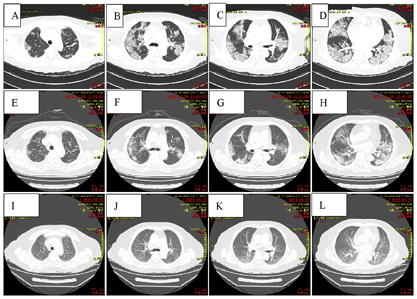

入院前辅助检查(2023年1月8日):全血细胞分析:红细胞计数4.27×1012/L,白细胞计数10.2×109/L,淋巴细胞计数0.86×109/L,中性粒细胞计数8.80×109/L,淋巴细胞百分比8.5%,中性粒细胞占比0.861,血小板计数363×109/L,余正常。肾功+电解质+肝功+心肌酶学+血脂全套:白蛋白30.0 g/L,白球比0.8,总胆红素24.3 μmol/L,门冬氨酸转移酶111.1 U/L,谷氨酰转肽酶115.0 U/L,尿素6.40 mmol/L,葡萄糖7.62 mmol/L,钾3.20 mmol/L,钙1.95 mmol/L,丙氨酸氨基转移酶46.8 U/L,胆碱酯酶2415.7 U/L,乳酸脱氢酶449.0 U/L,其余项目正常。凝血系统检查:纤维蛋白原6.74 g/L,凝血酶原比率1.18 g/L,D-二聚体6.45 mg/L,抗凝血酶Ⅲ 57.60%,凝血酶原活动度66.80%,纤维蛋白(原)降解产物21.35 μg/ml,余项正常。血清肌钙蛋白T 0.016 ng/ml,B型钠尿肽测定1920.0 pg/ml,C反应蛋白149.54 mg/L。新冠病毒核酸:阳性。新冠病毒抗原:阳性。肺部CT(图1):双肺病毒性肺炎;纵隔淋巴结肿大,部分钙化;主动脉、冠状动脉硬化。

经过治疗,患者发热、胸闷、气憋症状消失,咳嗽减轻,呼吸衰竭得到纠正(表4),新冠病毒被清除(表1),同时食欲改善,进食恢复,血象、血凝及生化指标逐渐恢复至正常水平(表2、表3、表5),各炎症标志物、N端钠尿肽基本降至正常水平,未继发真菌、细菌感染(表6)。1月29日复查肺CT显示肺部病灶面积较入院时吸收(图2A~2H),继续观察1周,于2月3日病情好转出院,叮嘱患者居家时继续氧疗,坚持俯卧位通气与呼吸操锻炼,口服利伐沙班抗凝(每次10 mg、1次/d),加强营养支持,患者肺功能明显改善,不吸氧状态下日常活动不受限,3月22日再次复查肺CT提示双肺病毒性肺炎吸收期改变,较1月29日范围缩小(图2I~2L);疾病顺利恢复,目前处于呼吸康复锻炼过程中。